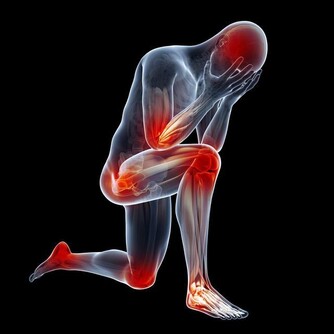

根據中醫經絡學說,人的五指尖各有經穴,而且分別與內臟有密切的關係,如果有一個指尖感到特別疼痛時,表示與此經穴相關的內臟已有了某種毛病。

您不妨將指甲的根部捏住然後用力壓並轉動,從小手指開始,一個一個的捏,感覺有沒有特別疼痛的手指。不同部位的疼痛感,預示身體的某個部位有毛病了。

在揉捏時如果發覺疼痛的部位即便是輕微疼痛,也和那個手指的穴位有關係,表示所屬的部位不正常。此時需要把那個部位的手指仔細揉搓,以使疾患快速好轉。